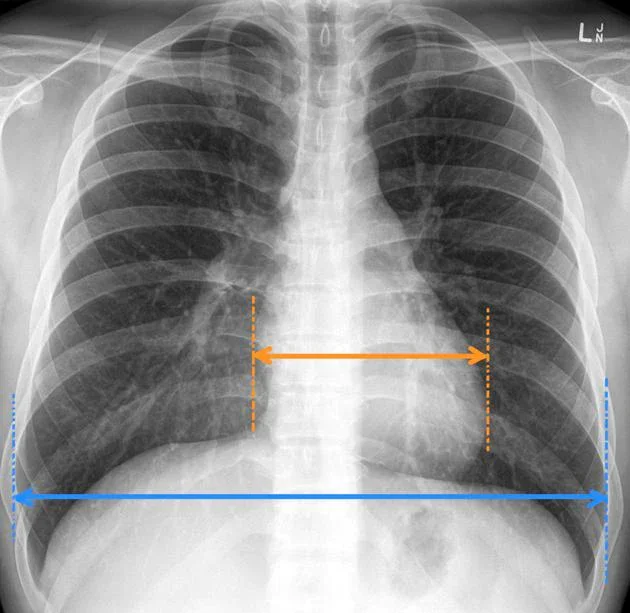

Кардио-торакален индекс KTИ - При рентгенография на бял дроб може да се измери кардиоторакалното съотношение и да се определи кардио-торакален индекс. Той показва съотношението на максималния хоризонтален диаметър на сърцето към максималния хоризонтален диаметър на гръдния кош.

Нормалните стойносто на КТИ са под 0,50 (между 0,42 и 0,50). Измерване под 0,42 обикновено се счита за патологично. Измерване над 0,50 обикновено се приема за анормално, въпреки че някои рентгенолози смятат, че измервания до 0,55 са „гранични“.

Сърдечна сянка - Представлява образът на сърцето и големите кръвоносни съдове върху рентгеновата снимка. Тъй като сърцето е плътен орган, на снимката изглежда като светло петно на фона на тъмните бели дробове. Нормалната сърдечна сянка на рентгенография на гръдния кош показва остър, добре дефиниран силует, като размерът на сърцето заема по-малко от 50% от максималния диаметър на гръдния кош (кардиоторакално съотношение КТИ по-малко от 0,5) на рентгенова снимка. Дясната граница се образува от дясното предсърдие, а лявата - от лявата камера. Когато резултатите не показват изменения в размера и положението на сърцето в разчитането обикновено се посочва, че е в норма или без особености (б.о.) - сърдечна сянка в норма, сърдечно-съдова сянка б.о., срединно разположена.